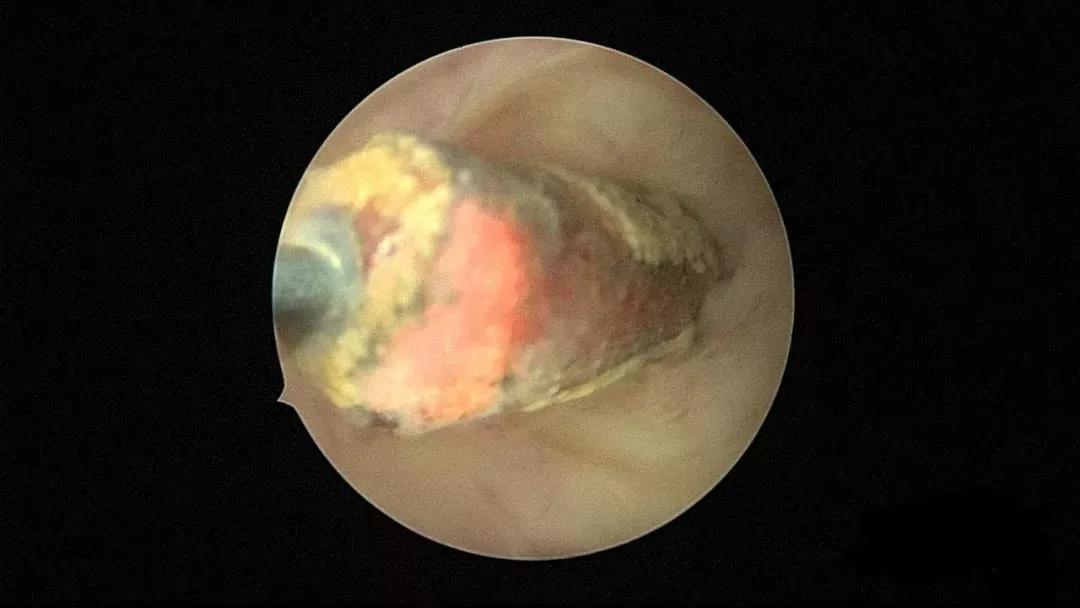

宫腔脓苔

女性绝经后半年内建议及时取出宫内节育器,B超提示节育器移位、异位、嵌顿、合并宫腔占位或宫腔积液时,建议行宫腔镜取节育器,同时取内膜或病变组织送病检。宫腔镜治疗宫腔积脓直视下操作,将脓液用膨宫泵低压冲洗干净,引流彻底,复发率低,不易造成子宫穿孔,术后抗炎治疗7~10天可治愈。如果宫颈萎缩明显时,术前给予米非司酮、米索前列醇或卡孕栓等预处理。